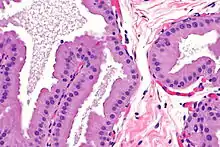

Apocrine metaplasia is a reversible transformation of cells to an apocrine phenotype. It is common in the breast in the context of fibrocystic change. It is seen in women mostly over the age of 50 years. Metaplasia happens when there is an irritation to the breast (breast cyst). Apocrine-like cells form in a lining of developing microcysts, due to the pressure buildup within the lumen. The pressure build up is caused by secretions.[4] This type of metaplasia represents an exception to the common rule of metaplasia increasing the risk for developing cancer in that apocrine metaplasia doesn't increase the possibility of developing breast cancer.[5]

Apocrine ductal carcinoma in situ (ACDIS) is a very rare breast carcinoma which is regarded as a variant of the ductal carcinoma in situ breast tumors. ACDIS tumors have microscopic histopathology features that are similar to pure apocrine carcinoma of the breast tumors but differ from them in that they are completely localized, i.e. have not invaded nearby tissues or metastasized to distant tissues.[6]

Apocrine carcinoma is a very rare form of female breast cancer. The rate of incidence varies from 0.5 to 4%.[7] Cytologically, the cells of apocrine carcinoma are relatively large, granular, and it has a prominent eosinophilic cytoplasm.[8] When apocrine carcinoma is tested as a “triple negative", it means that the cells of the patient cannot express the estrogen receptor, progesterone receptor, or HER2 receptor.[9]